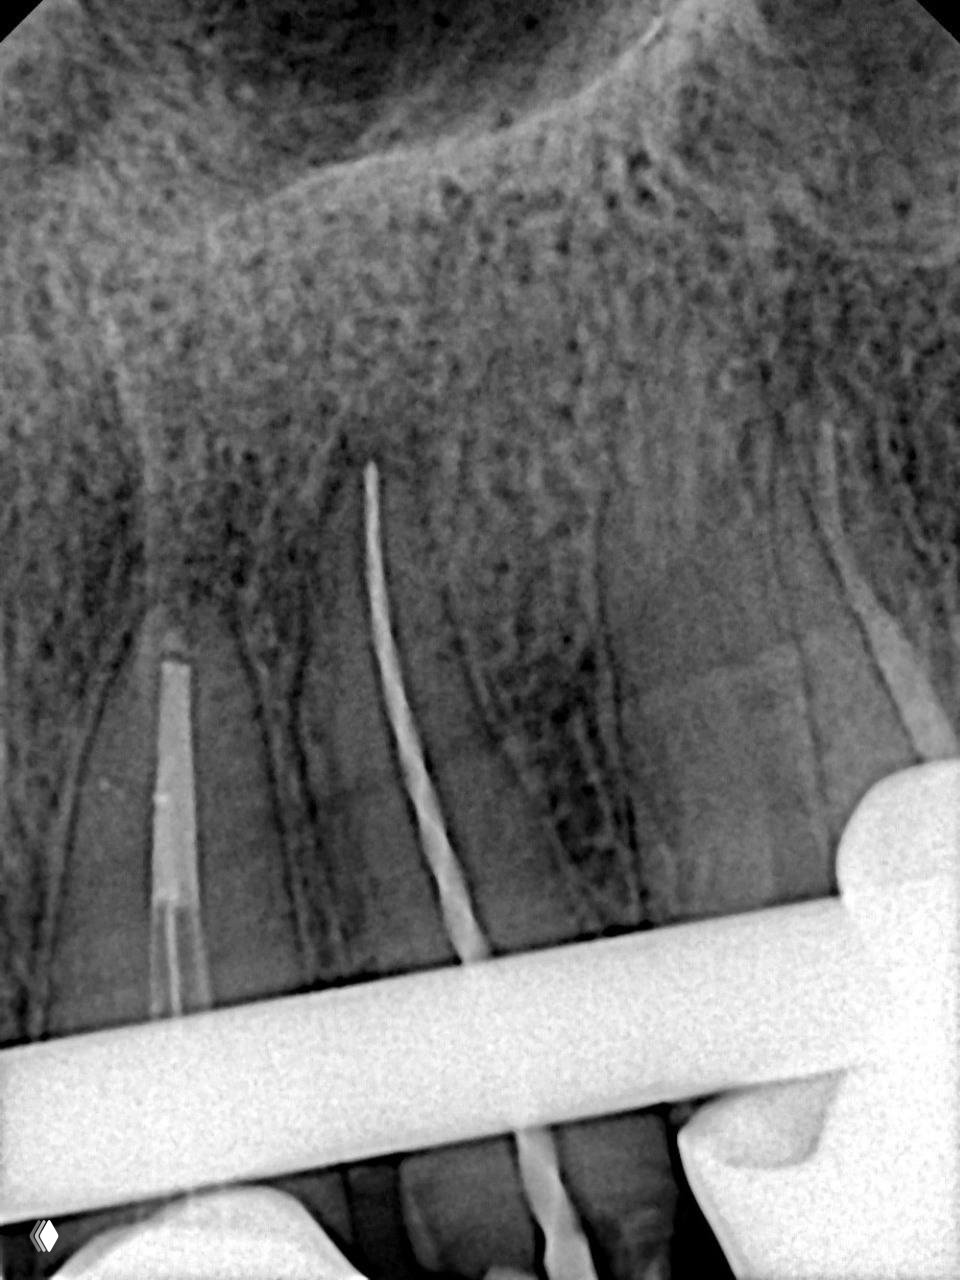

Что делать, если сидишь себе работаешь уверенно, и тут бац 💥 обломок файла или эндочака сломался в апикальной части.

Спокойно, друзья, сейчас расскажу, как я справилась с этой ситуацией в реальном клиническом случае, и вы увидите, что это совсем не приговор для зуба и не повод для паники 🙌

‼️ И так, первое и самое главное: байпас ручными инструментами

Я начала с ручных К-файлов, прошла последовательно от 10 до 20, аккуратно, без спешки 🎯 Затем перешла на машинные Eighteeth Blue в последовательности 15.04, 20.04, 25.04, 30.04, и вот тут уже открывается пространство для маневра.

Тогда ваша задача определить, где находится внутренняя кривизна корневого канала, поставить туда насадку для извлечения (например ET25), сделать аккуратные вертикальные движения, и обломок буквально всплывёт наверх, как будто сам захотел выбраться оттуда 😄 ну или его заставили

Тут мы продолжаем байпас машинными файлами до 35.04, а потом берём 25.04 и запускаем его на моторе против часовой стрелки, и он как маленький помощник вытягивает обломок наверх 🪄